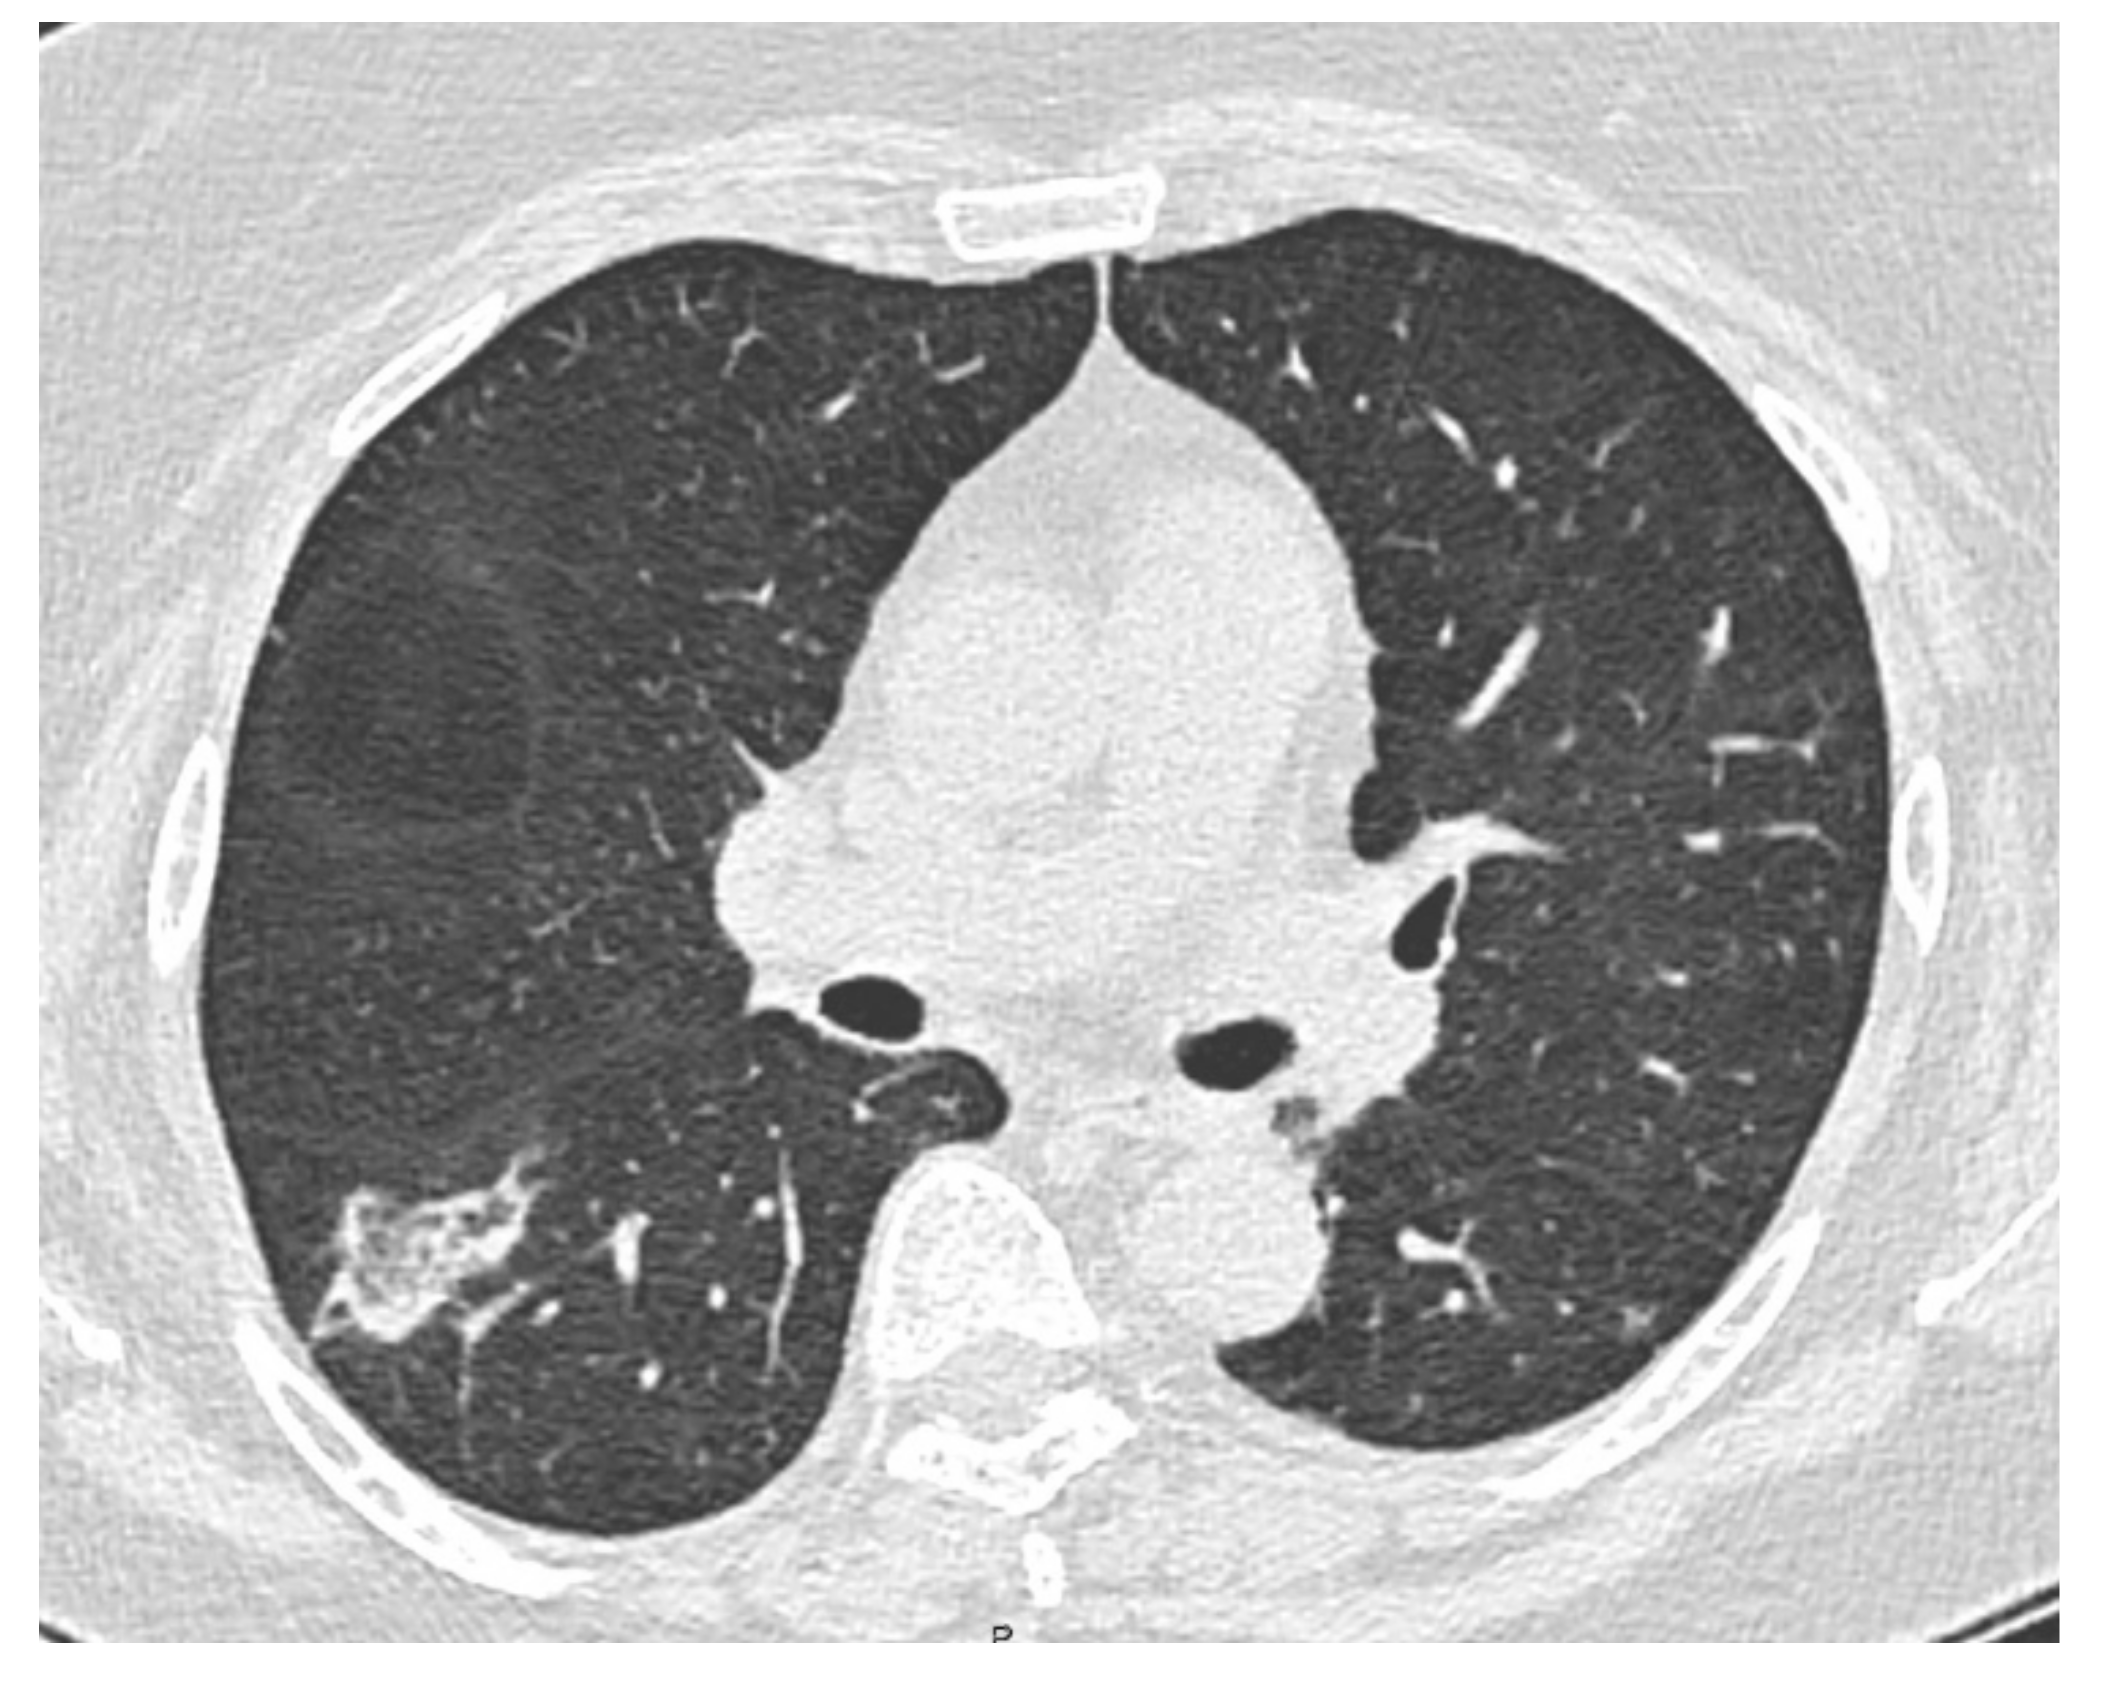

Diagnosis of Organizing Pneumonia with an Ultrathin Bronchoscope and Cone-Beam CT: A Case Report

2. Case Presentation